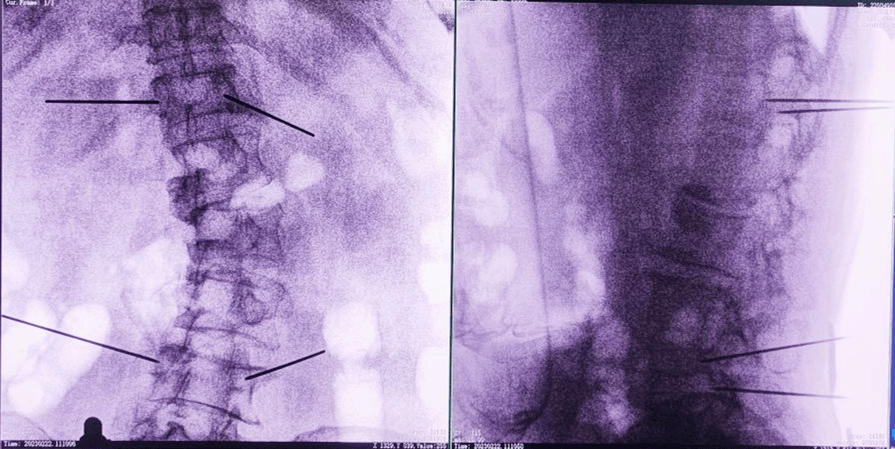

經(jīng)皮椎體成形術(shù),也就是俗稱的“骨水泥手術(shù)”。骨水泥是一種高分子材料,在凝固以前,骨水泥是膠狀的;凝固之后則硬的像骨頭一樣。治療的時(shí)候,醫(yī)生首先要在X光的引導(dǎo)下找到病人骨折的脊椎,之后把一根毛衣針粗細(xì)的中空穿刺針,通過皮膚穿刺到受損的椎體內(nèi)。

主任為患者注射骨水泥,再次影像掃描后,發(fā)現(xiàn)骨水泥進(jìn)入位置非常好,彌散效果更佳,手術(shù)順利完成,患者的恢復(fù)也自然更好。